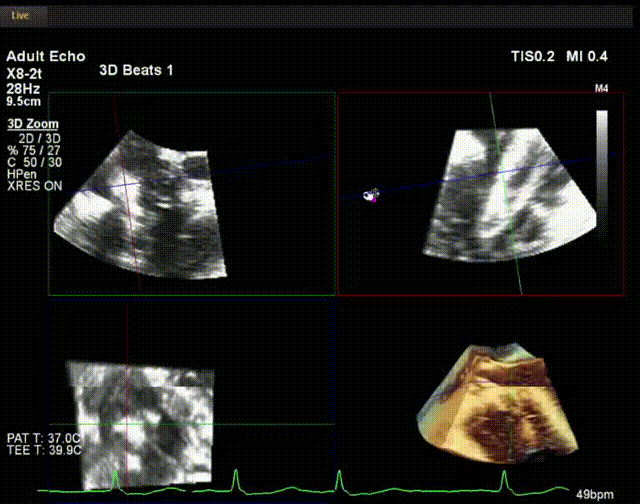

術(shù)中超聲

手術(shù)在全麻狀態(tài)下開(kāi)展,此次手術(shù)采用經(jīng)頸靜脈入路的方式。在TEE及DSA雙重引導(dǎo)下,術(shù)者調(diào)整輸送器頭端角度使得其與三尖瓣瓣環(huán)平面垂直。在輸送器進(jìn)入右心室后釋放室間隔錨定裝置,而后釋放瓣葉夾持件(2個(gè)耳片結(jié)構(gòu))成垂直狀態(tài)。在TEE及DSA確定夾持件固定至三尖瓣葉根部且位于右室側(cè)后釋放人工瓣心房側(cè)盤(pán)片。隨后調(diào)整瓣膜同軸性以及室間隔錨定件位置(貼合室間隔),進(jìn)而釋放室間隔錨定裝置,并再次確認(rèn)瓣膜位置、穩(wěn)定性及同軸性,解離人工瓣膜與輸送器間連接,并撤出輸送器,完成了LuX-Valve Plus人工三尖瓣瓣膜的植入。